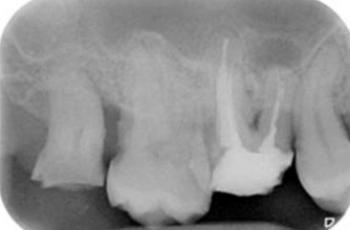

Absceso periodontal Nueva Clasificación Workshop 2017 | UCM Absceso periodontal Casos Clínicos E.T.E.P. – Nueva Clasificación Este proyecto de Casos Clínicos... Periodontitis, estadio IV, grado C Nueva Clasificación Workshop 2017 | UCM Periodontitis, estadio IV, grado C Casos Clínicos E.T.E.P. – Nueva Clasificación Este proyecto de Casos Clínicos... Periodontitis, estadio II, grado A Nueva Clasificación Workshop 2017 | UCM Periodontitis, estadio II, grado A Cátedra Extraordinaria DENTAID en Investigación Periodontal La Cátedra Extraordinaria... Tratamiento de un diente uniradicular afectado por una lesión... Tto. Periodontal | USC Tratamiento de un diente uniradicular afectado por una lesión... Con frecuencia nos encontramos ante la cuestión de tratar de conservar un diente con pronóstico cuestionable o... Tratamiento de un paciente con periimplantitis Tto. Periimplantario | UCM Tratamiento de un paciente con periimplantitis Presentamos un caso clínico sobre el tratamiento de un paciente con periimplantitis, elaborado... Tratamiento de un paciente con periodontitis crónica I Tto. Periodontal | UCM Tratamiento de un paciente con periodontitis crónica I Presentamos un caso clínico, elaborado por los Doctores Eduardo Montero y David Herrera de la... Efectividad del Tratamiento en Periodontitis Agresiva Tto. Periodontal | UIC Efectividad del Tratamiento en Periodontitis Agresiva El mantenimiento de la dentición natural en estado de salud ha sido un objetivo importante en... Lesión endo-periodontal combinada verdadera en raíz mesiovestibular de... Tto. Periodontal | USC Lesión endo-periodontal combinada verdadera en raíz mesiovestibular de... Presentamos un caso clínico sobre un paciente que acude a la clínica dental por molestias generalizadas.... Tratamiento multidisciplinar de un paciente con Periodontitis avanzada... Tto. Periodontal | USC Tratamiento multidisciplinar de un paciente con Periodontitis avanzada... Las enfermedades periodontales tienen una elevada prevalencia en la población adulta en España....